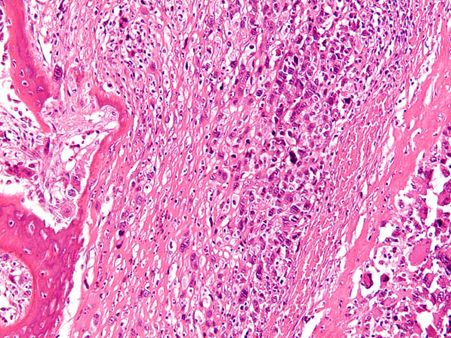

সার্কোহেল্প (Sarcohelp.org) এ প্রকাশিত একটি রিপোর্ট অনুযায়ী, অস্টিওসারকোমা হল এক ধরনের হাড়ের ক্যান্সার বা বোন ক্যান্সার, যা শরীরের লম্বা হাড়ে হতে দেখা যায়। আক্রান্ত স্থানে টিউমারের মত ফুলে যায়। ক্যান্সার সোসাইটি জানাচ্ছে যে, সমস্ত হাড় সংক্রান্ত ক্যান্সারের মধ্যে অস্টিওসারকোমা-ই সবথেকে বেশি হতে দেখা যায়। এটি মূলত হাড়ের অস্টিওব্লাস্ট কোষে দেখা যায়।

অস্টিওসারকোমাকে তিন ভাগে ভাগ করা হয়।

১) হাই গ্রেড

২) ইন্টারমিডিয়েট গ্রেড

৩) লো গ্রেড

লক্ষণগুলির উপর ভিত্তি করে পরিবার এবং ব্যক্তিগত ইতিহাস জানার পর একটি পরীক্ষার মাধ্যমে এই রোগ নির্ণয় করা হয়। রোগ নির্ণয় সংক্রান্ত পরীক্ষাগুলি এক বা একাধিক বার করতে হতে পারে। বায়োপসি, এক্স-রে, বোন স্ক্যান, এমআরআই, সিটি স্ক্যান এর মাধ্যমে নির্ণয় করা হয়।

আক্রান্ত ব্যক্তির শারীরিক অবস্থার উপর নির্ভর করে এবং ক্যান্সারের স্টেজ এর উপর ভিত্তি করে কেমোথেরাপি ও রেডিয়েশন থেরাপির মাধ্যমে চিকিৎসা করা হয়। এছাড়াও সার্জারির মাধ্যমে এই রোগের চিকিৎসা করা হয়।